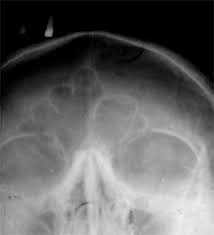

부비동염은 뺨·이마·코 주변 얼굴뼈 속 ‘부비동’이라는 공간에 염증이 생긴 상태를 말합니다.

정상적으로는 공기로 차 있어 가볍고 압력이 일정하지만, 염증이 생기면 고름·점액이 차면서 통증, 압박감, 코막힘 등이 발생합니다. 급성으로 시작해 4주 이내면 급성 부비동염, 12주 이상 지속되면 만성 부비동염으로 분류됩니다.